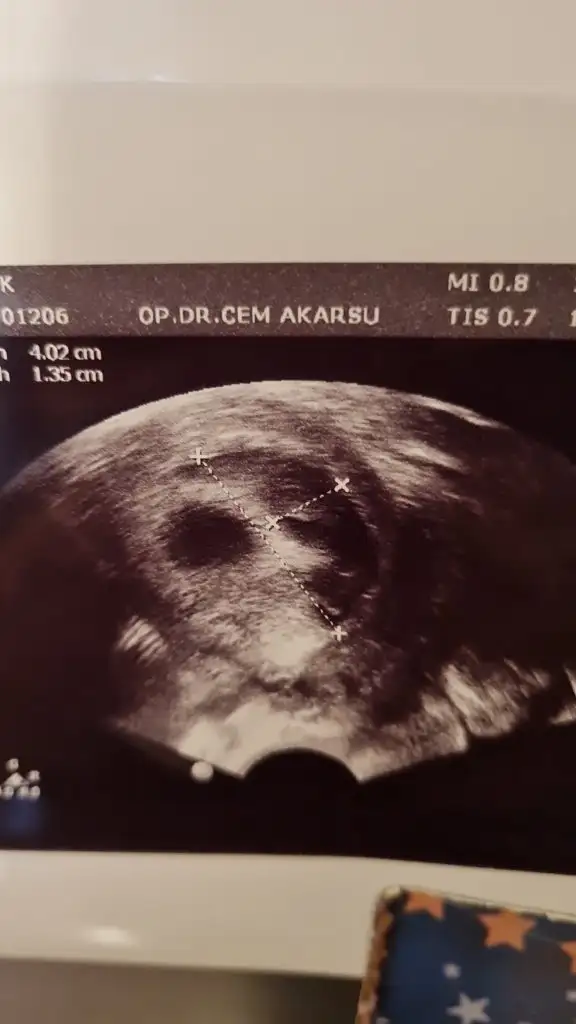

Öncelikle geçmiş olsun ama bak çok şükür bebeğin gelişimi, kesesi çok iyimiş canım. Sıkma canını dikkat et bol bol dua inşallah. Bide neden çoğalabilirmiş sordun mu? Sende gün aşırı kahverengi akıntı falan oluyor muydu?kizlar sabah gittik doktora bu sefer karindan bakti o yuzden aynalama oldu kan alani sagken solda gorundu resim eklicem ama hic azalma olmamis aksina cogalmis gorur gormez survivor geliyo insallah dedi cok uzun zamandir bukadar buyuk kanama alani gormemistim ama bebek haftasi olarak boyut gelisim kese olarak gayeet iyi durumda cok kucuk bi alana tutunmus orda buyumeye calisiyo dedi allah askina dua edin bebegime zarar gelmesin su kanama alani kuculsun sagligina kotu bisey olmasin

tukenmez kalemle cizili ultrason bu haftaki